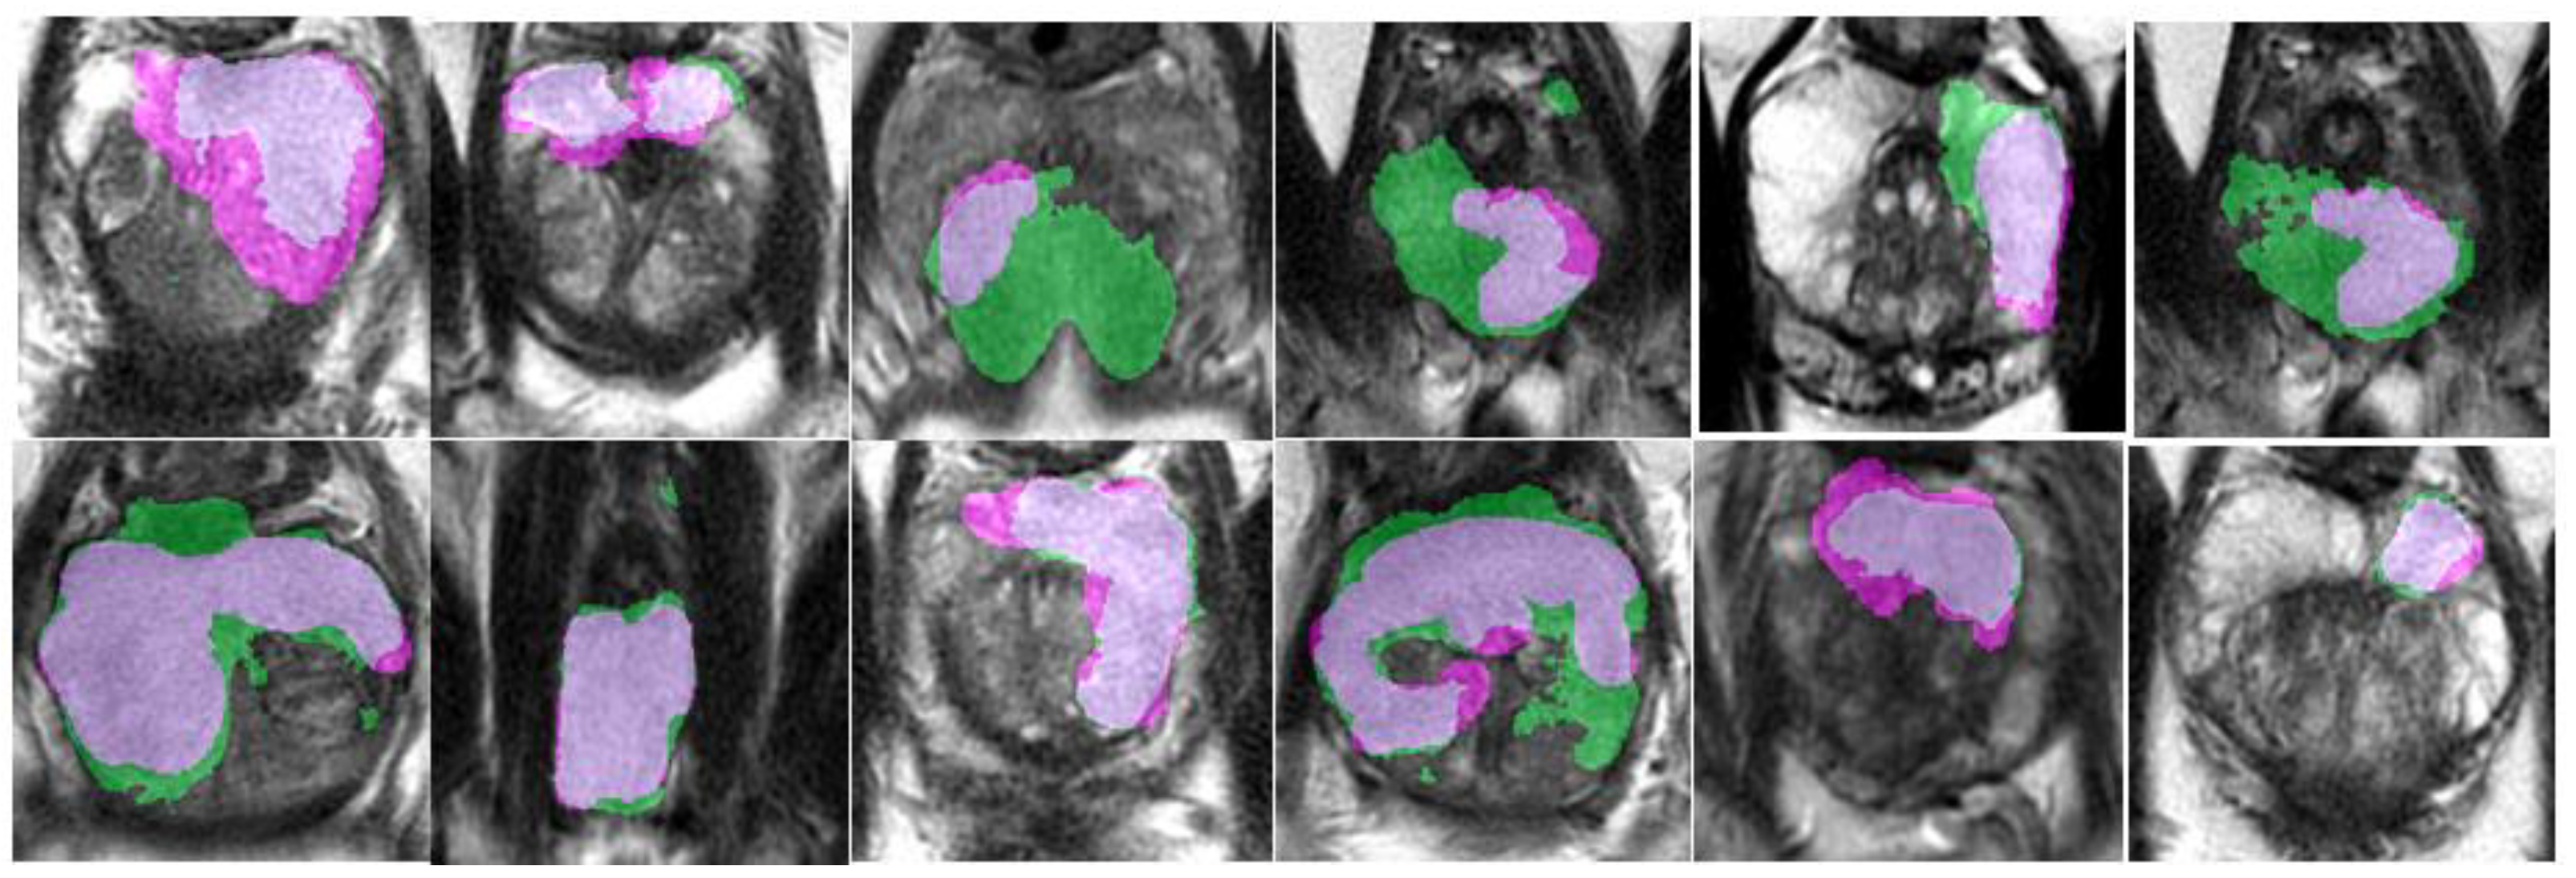

An example of segmentation of cancer foci by the final 2D cancer segmentation model is shown in Figure 17.

Figure 17. Segmentation of cancer by the final 2D segmentation model.